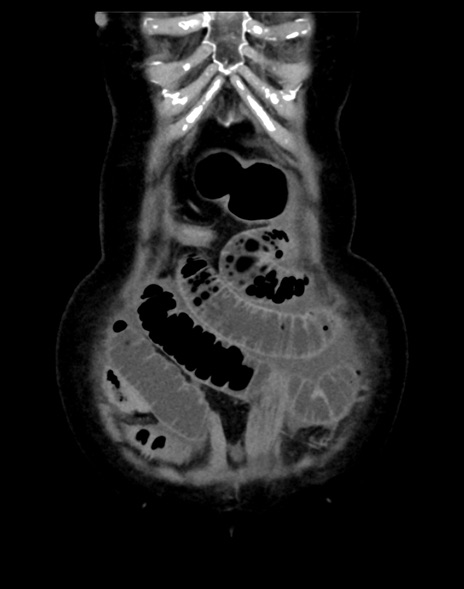

症例13 CT(冠状断像)1日半後